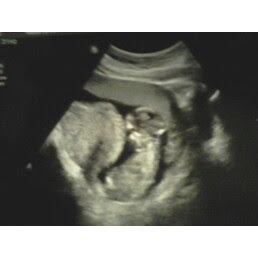

I suppose I've waited long enough to talk about my current condition. SO, here it goes...I am currently 18 weeks pregnant. I am due on October 1st. I had an ultrasound on the 20th of April and I found out that I will be having a baby boy! His name will be Sullivan Oxford Simons. McKenna is so excited to be a big sister and she is so sweet with my tummy. She loves to rub, tickle and kiss her brother and she is always making sure that he is OK. I know that she will be a wonderful helper with him. I am insanely excited and scared at the same time. My children will be a "matching set"; McKenna and Sulli have the same daddy. We were trying to be a family and spend a lot of time together as a family and well...yeah the whole pregnancy thing was a result of that. He and I are not together in the slightest. Anyways, there you have it. Here are some of the ultrasound pics.

Sulli at 13 weeks

It's a BOY!!!